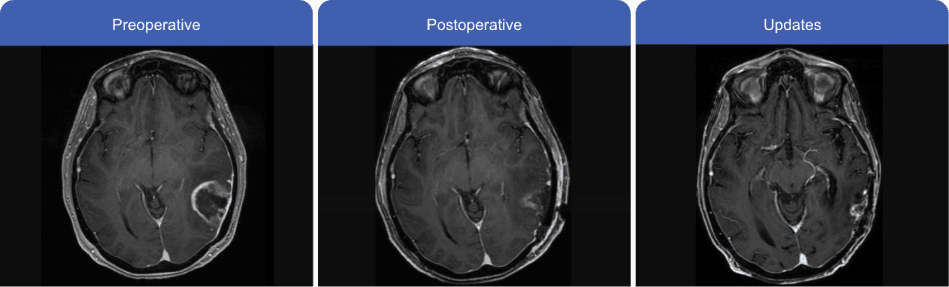

Patient's MRI

Case information used with permission from Gautam Prasad, MD, PhD.